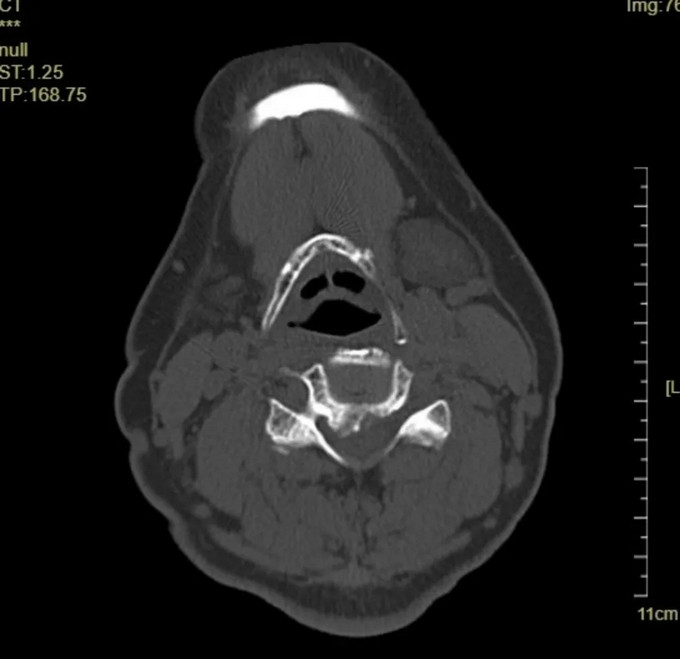

頸椎CT橫斷位 可以看到明顯突出的骨贅

頸椎MRI橫斷位